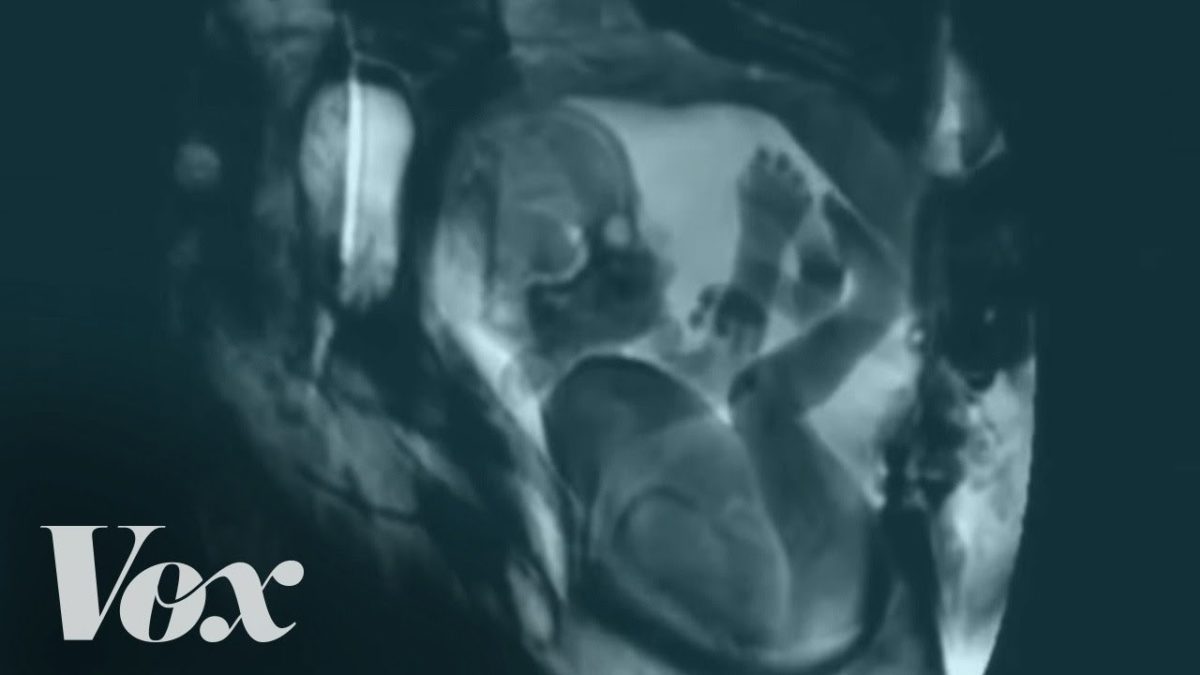

Με ένα εντυπωσιακό βίντεο, η ομάδα του Vox, έρχεται να μας λύσει κάθε τέτοια απορία, με την βοήθεια ενός μαγνητικού τομογράφου.

Η μαγνητική τομογραφία “βλέπει” το εσωτερικό του σώματος με τη χαρτογράφηση της θέσης των μορίων του νερού, τα οποία υπάρχουν σε διαφορετικές πυκνότητες σε διαφορετικούς τύπους ιστού.

Θα δείτε ανθρώπους να μιλούν, να φιλιούνται, να κάνουν σεξ (!), να πίνουν χυμό, ακόμη και παίζουν ένα μουσικό όργανο. Πρόκειται για ένα βίντεο, στο οποίο συγκεντρώθηκαν εικόνες από παλιότερα αντίστοιχα βίντεο από διάφορες πηγές, όπως οι εικόνες που υπήρχαν σε έρευνα του 1999 στην επιστημονική επιθεώρηση British Medical Journal.

Μάλιστα, οι εικόνες από μαγνητικό τομογράφο την δεκαετία του 1960 έδειξαν ότι είναι εφικτό καταγραφεί σε βίντεο η γυναικεία σεξουαλική διέγερση, καθώς και η ανατομική αντίδραση τόσο των αντρικών όσο και των γυναικείων γεννητικών οργάνων κατά τη συνουσία. Οι σαρώσεις βοήθησαν τότε τους ερευνητές να αποδείξουν ότι το πέος δεν έχει σχήμα S, αλλά μάλλον ένα σχήμα “μπούμερανγκ” στην ιεραποστολική στάση στο σεξ και πως η μήτρα δεν αυξάνεται σε όγκο κατά τη διάρκεια της σεξουαλικής διέγερσης.